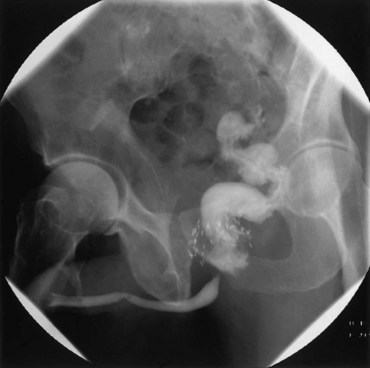

Vesicovaginal fistulae (VVF) are the most common acquired fistula of the urinary tract (Gerber and Schoenberg, 1993) and have been known since ancient times (Fig. 77–1). However, it was not until 1663 that Hendrik von Roonhuyse first described surgical repair of VVF by denuding the fistula margins and then reapproximating them with sharpened stiff swan quills (Margolis and Mercer, 1994). Johann Fatio is generally credited with the first successful VVF repair, in 1675, using von Roonhuyse’s technique (Falk and Tancer, 1954). In 1838, using leaden suture, John Peter Mettauer was the first U.S. surgeon to claim a successful VVF closure (Kight, 1967). In 1852, James Marion Sims published his now famous surgical series describing his method of surgical treatment of VVF using silver wire in a transvaginal approach (Sims, 1852). Of note, it was not until his 30th attempt at closure of VVF that he achieved success. However, Sims remains the subject of considerable debate regarding his ethics (Richardson, 1994; Sartin, 2004), because it is unknown whether the patients in his surgical series were willing and consenting participants (all were African-American slaves in pre–Civil War America). He was later to become one of the great figures in the history of operative gynecology. The first successful transabdominal approach to VVF repair was reported by Trendelenburg in 1888, and the concept of an interpositional flap was first proposed and reported in 1928 by Martius, who used a labial fat pad.

Figure 77–1 Voiding cystourethrogram demonstrates filling of the vagina with voiding due to a post-hysterectomy vesicovaginal fistula.